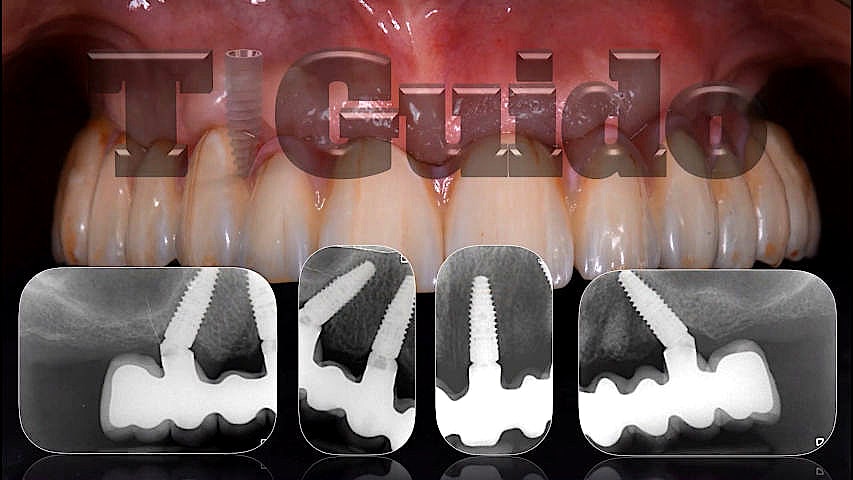

Alcuni nostri casi